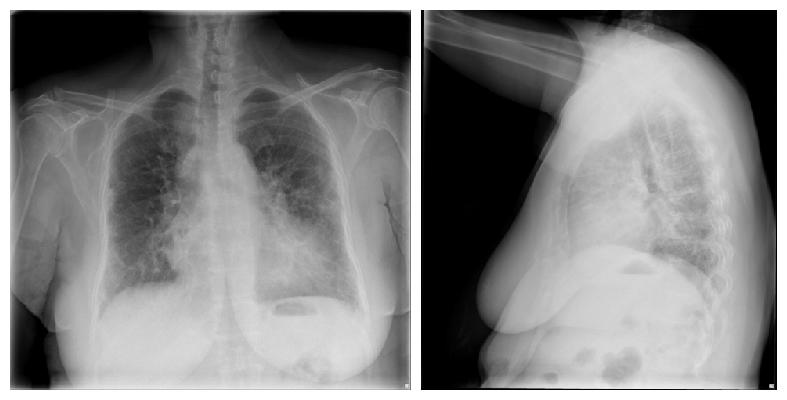

Refer to caption

UID: CXR1001

Impression: Diffuse fibrosis. No visible focal acute disease.

Indication: dyspnea, subjective fevers, arthritis, immigrant from Bangladesh

Findings: Interstitial markings are diffusely prominent throughout both lungs. Heart size is normal. Pulmonary XXXX normal.

Problems: Markings; Fibrosis

MeSH: Markings/lung/bilateral/interstitial/ diffuse/prominent; Fibrosis/diffuse

Figure 1: An example from the IU chest X-ray dataset, which shows an abnormal case with findings. We highlight the sentences with our human abnormality annotation, i.e., normal sentences are written in blue and abnormal sentences in green.

For our work, we use the Indiana University chest X-ray Collection [Demner-Fushman et al.(2015)Demner-Fushman, Kohli, Rosenman, Shooshan, Rodriguez, Antani, Thoma, and McDonald] (IU chest X-ray dataset), which contains 7,470 chest X-Ray images with multiple annotations. These include indication, findings, impressions in a textual form and MTI (Medial Text Indexer) encodings. The MTI encodings are automatically extracted keywords from the indication and findings. We identify 121 unique MTI labels in dataset and use these labels for an additional training signal. Additionally the authors manually annotated the images with MEDLINE® Medical Subject Headings® (MeSH®). To summarize, this public dataset contains 3,955 narrative reports, each associated with MeSH tags and two views of the chest, i.e., a Posteroanterior (PA) and a lateral view. We set the doctor’s report to be the concatenation of the impression and findings similarly to other works [Jing et al.(2018)Jing, Xie, and Xing, Wang et al.(2018)Wang, Peng, Lu, Lu, and Summers]. We show one example from this dataset in Figure 1.